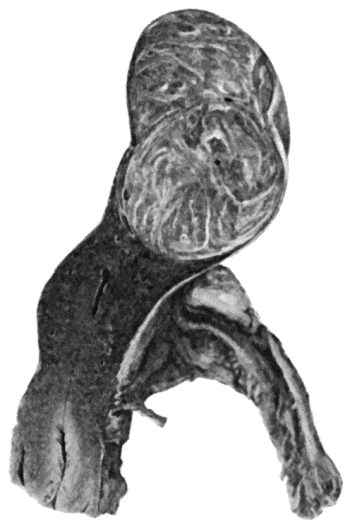

133.Skeleton of Rickety Dwarf 470

142.Multiple Chondromas of Phalanges and Metacarpals 488

143.Skiagram of Multiple Chondromas 489

144.Multiple Chondromas in Hand 490